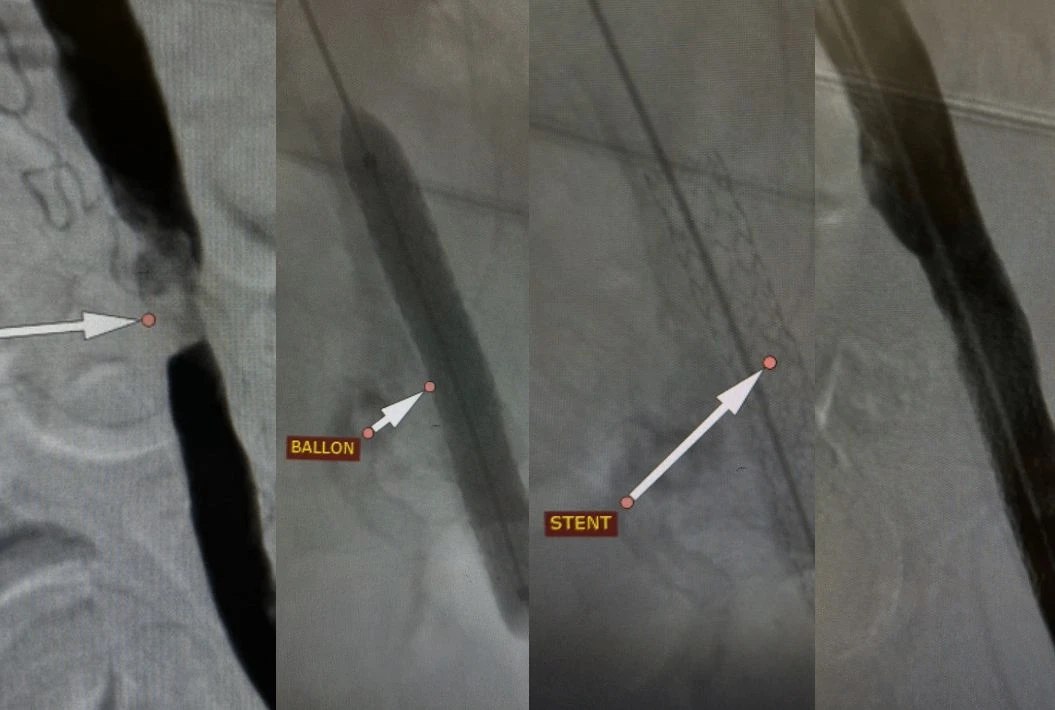

Единственным шансом стало проведение малотравматичного эндоваскулярного вмешательства — стентирования подвздошной артерии. Операцию выполнила команда рентгенэндоваскулярных хирургов под руководством заведующего отделением Андрея Легкого.

— Мы провели стентирование через небольшой прокол, что позволило быстро восстановить кровоток. Уже через сутки после процедуры пациент мог самостоятельно передвигаться и был выписан из стационара для дальнейшего восстановления, — прокомментировал Андрей Легкий.